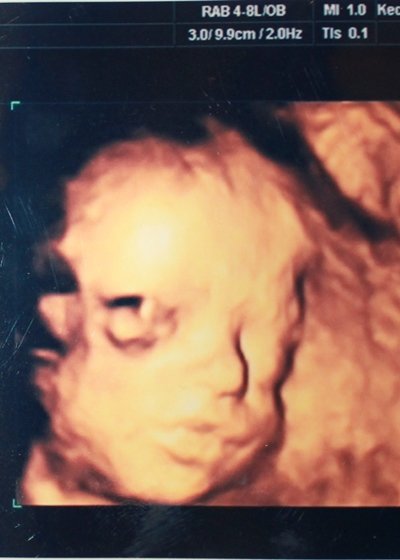

Babapofik!

Szerintem is nagyon különböznek!

Az enyém tiszta apósom, ugyan így csücsörít Ő is

Meg látszik, hogy fiús a pofija!

Mesi, 28. hét

Mesi, 28. hét

Poci fotó

Poci fotó